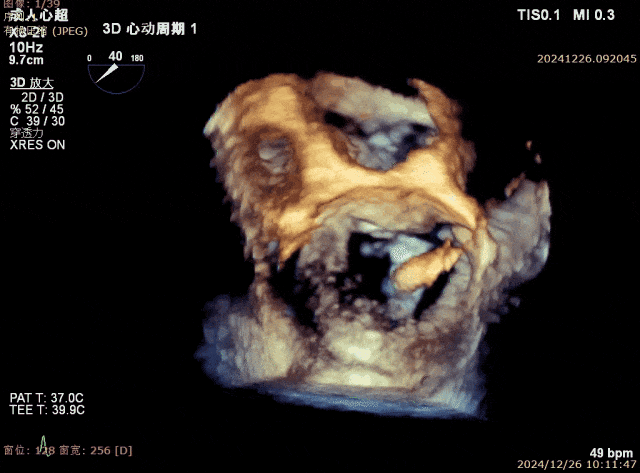

患者为68岁男性,3月前出现气短,活动后明显,休息可缓解,无明显胸痛,无夜间呼吸困难,就诊当地医院考虑“肺炎、心衰”,给予对症治疗好转,具体不详,无明显发热,无咳嗽咳痰,出院后未规律服药。10天前,气短再发,就诊当地医院心脏彩超提示二尖瓣后叶腱索断裂,二尖瓣关闭不全伴重度反流。左心增大,室间隔增厚,肺动脉高压,三尖瓣轻度反流,主动脉瓣中度反流。心电图提示房颤,左室肥大。为进一步诊治入院。经食道超声提示:患者二尖瓣后叶脱垂伴腱索断裂,前叶2.6cm,后叶1.4cm,脱垂宽度16mm,脱垂高度8mm,瓣口面积6.0cm²。

术前影像